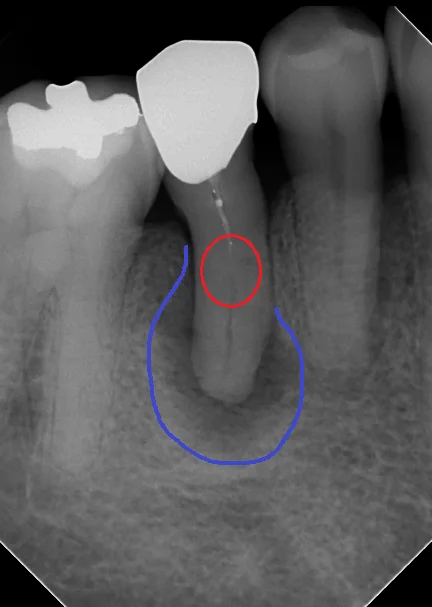

例えば、この方ですが・・・

分かりますかね?

根の中央付近で神経の管が封鎖されているため、前の先生ではそれ以上に触れなかったのかそのままお薬を詰めている状態になっており、神経の管の下の方に何も入っていない状況になっています。

すこし分かりやすい様にマークを入れるとこういう感じです。

根管が閉塞しているのが、赤丸の部分です。そこの上の方には白い薬剤が軽く入っていますが、下の方には何も入っていないのが分かると思います。

画像上で青くしている所が膿が溜まっている箇所になります。

非常に広範囲に膿が溜まっていますね。